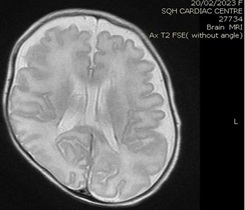

Brain MRI (images 1,2,3,4) at the age of 78 days; revealed that generalized relative simplified gyral pattern, generalized enlarged subarachnoid spaces as well as enlarged bilateral sylvian fissures, no diffusion restriction, no intracerebral hemorrhage, pituitary fossa appears normal in size, the posterior pituitary spot is not well defined.

Image 1

We were able to manage hypernatremia and polyuria with desmopressin and weaned the infant from a high fluid intake to a normal fluid intake per day [10-14]. The desmopressin response validated the diagnosis of central diabetes insipidus. Brain MRI data were also indicative of a central origin, particularly the posterior pituitary spot, which was not well delineated.  In comparison with previously reported cases, we controlled the case with a little dosage of oral desmopressin, and oral desmopressin is more practical than intranasal dDAVP treatment [15,16], and oral desmopressin administration and modification of dosage is easier than nasal application [17].